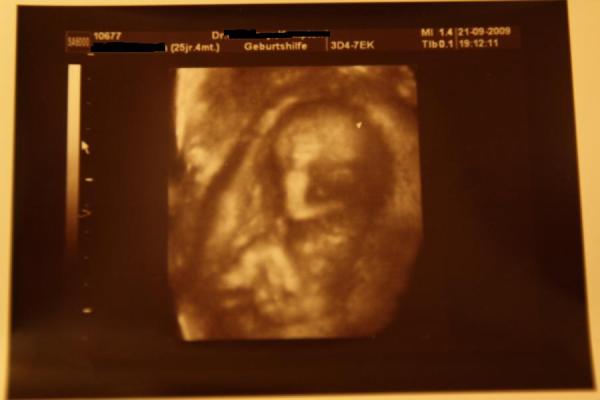

Hallo Mädels, komme gerade vom FA... Baby gehts super, ist zeitgerecht entwickelt. Ca. 8 cm SSL. Was es wird hat es nicht richtig gezeigt, hätte beides sein können... ich tendiere zu Bub!! Freu mich riesig, dass alles i. O. ist!!! lg Manu und n schönen Abend

Bild zu Zurück vom FA mit 3D Bildchen - Forum für März - Mamis